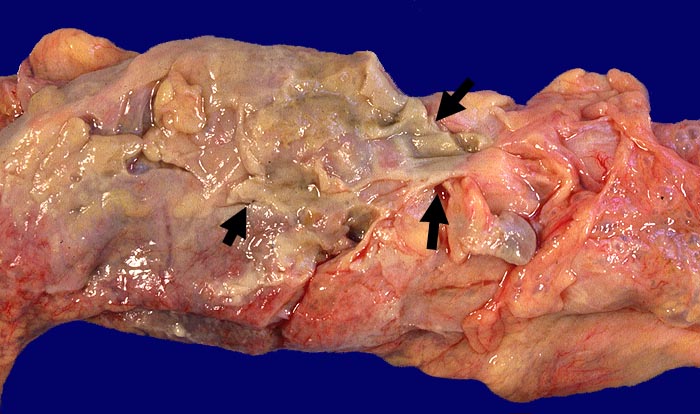

Divertikulitis

Makroskopie

Pathologischer Befund